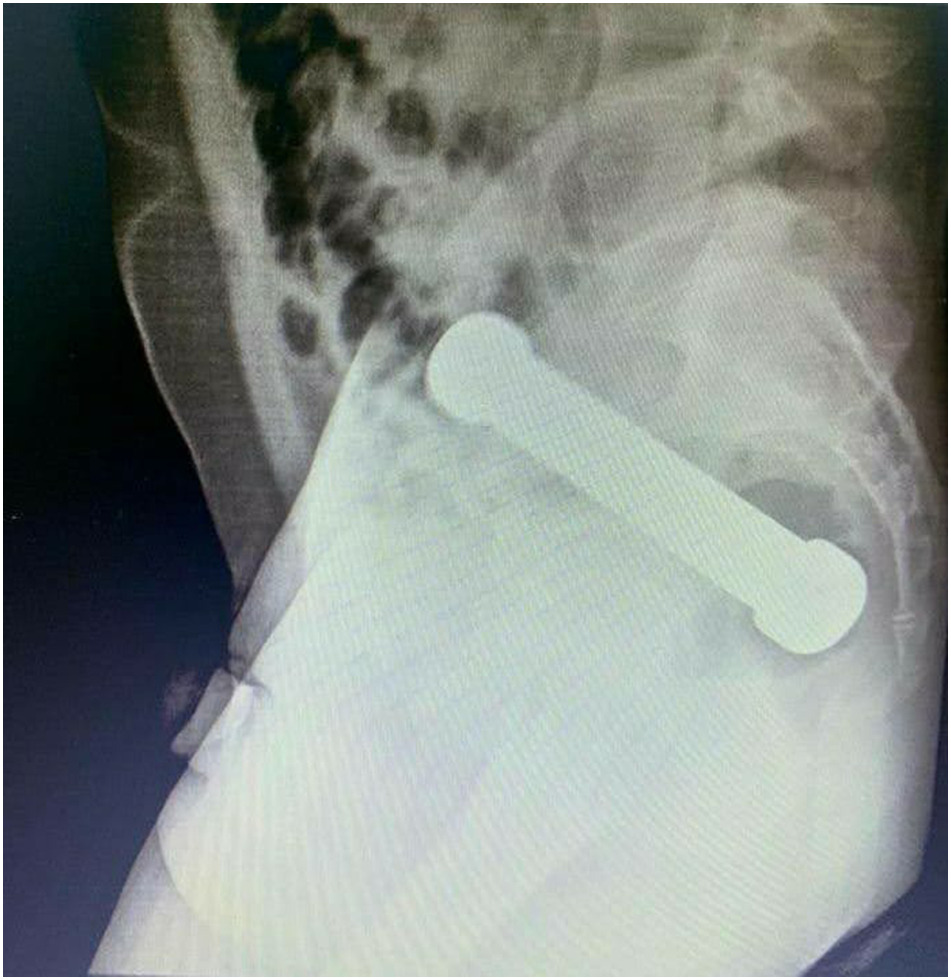

Tras realizarse un examen rectal que no entregó resultados concluyentes, se le realizó una radiografía, con lo que finalmente determinaron que tenía una mancuerna de dos kilos insertada en una parte profunda de su intestino grueso.

El hombre tenía una mancuerna de 20 centímetros atorada a la altura donde el colon se conecta con el recto que se había introducido dos días antes. ¿La solución? Los doctores realizaron una "extracción manual", donde uno de los funcionarios tuvo que introducir su antebrazo en el hombre.